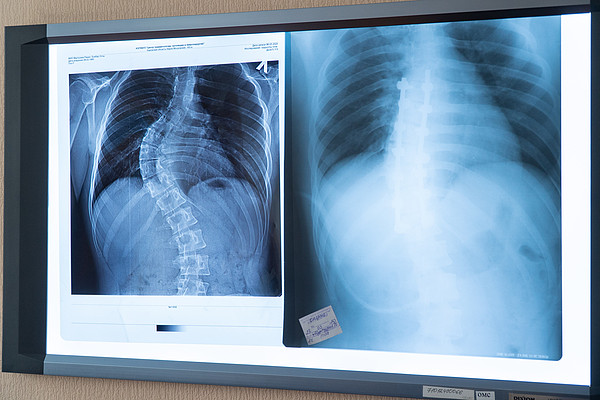

Кировские врачи выполнили сложнейшую операцию на позвоночнике